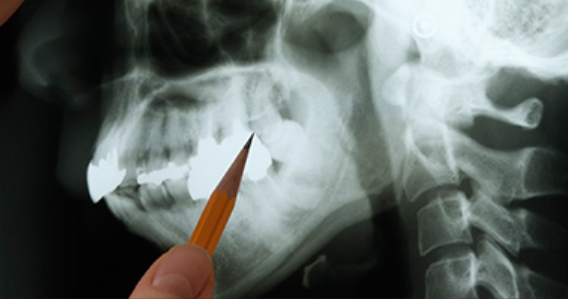

매복된 사랑니는 3D 첨단 CT촬영으로 상태를 정밀검사하고 발치계획을 세웁니다.

사랑니 발치 시에는 뿌리가 신경관과 근접해 있는지 또 어느쪽으로 휘어져 있는지를

파악해야

훨씬 더 안전하고 편하게 또 빠르게 뽑을 수 있습니다.

최첨단 3차원 CT를 이용하여 사랑니 뿌리의 위치와

신경관 위치 등을 정밀하게 분석한 후 시행하고 있습니다.